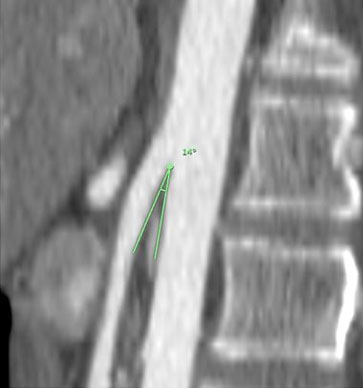

The patient presented intense epigastric pain, vomiting, and constipation, requiring hospitalization. Symptoms subsided when lowering enteral nutrition infusions up to 20 cc/h, and exacerbated when enteral nutrition volume was increased. The physical exam showed a normal abdomen, no distension, soft, with slight sensitivity at the epigastrium and no signs of peritoneal irritation. By this time, the patient’s weight was 36 kg, reaching a body mass index (BMI) of 16.8 kg/m2. An upper digestive endoscopy showed an esophageal stricture with actinic appearance, requiring endoscopic dilation. However, since stenosis does not explain the feeding intolerance, a CT scan was performed. It reported a significant decrease in intra-abdominal fat, especially in the retroperitoneal fat panniculus, associated with a change in caliber and dilation of the second and third portion of the duodenum (Figure 1 and Figure 2), possibly due to partial compression of the third portion between the aorta and the SMA. No other signs of intestinal obstruction were observed. Superior mesenteric artery syndrome was suspected so the images were reviewed with the radiologist, finding an aorto-mesenteric angle of 17° (Figure 3) and an aorto-mesenteric distance of 7.3 mm (Figure 4).

Figure 3: Reduced aorto-mesenteric angle in patient no. 1, sagittal view.